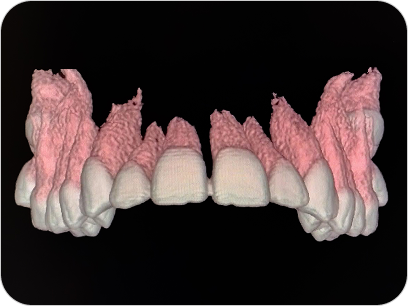

Dental Scan (Tomografía 3D Dental)

El Dental Scan o Tomografía Computada de Haz Cónico (CBCT) es un estudio especializado que brinda imágenes tridimensionales de alta resolución del sistema dentomaxilofacial. Es fundamental en odontología avanzada, permitiendo planificaciones precisas y diagnósticos más seguros.

La tomografía dental (CBCT) es un estudio esencial en odontología avanzada, que permite ver el maxilar, mandíbula y piezas dentales en 3D para diagnósticos y tratamientos más seguros.

UTILIDAD

- Planificación de implantes dentales.

- Evaluación de muelas del juicio y piezas retenidas.

Diagnóstico de quistes, lesiones óseas o problemas articulares.

VENTAJAS

- Imágenes 3D de alta resolución.

- Baja radiación.

- Ideal para odontología, ortodoncia y cirugía maxilofacial

¿PARA QUÉ SE UTILIZA?

- Planificación de implantes dentales con medición exacta del hueso.

- Evaluación de muelas del juicio o dientes incluidos.

- Estudio de quistes, tumores o lesiones óseas de mandíbula y maxilar.

- Diagnóstico de patología articular (ATM).

- Detección de fracturas, reabsorciones o infecciones profundas.

- Cirugías ortognáticas y procedimientos maxilofaciales complejos.

¿POR QUÉ ES UN ESTUDIO DESTACADO?

- Imágenes en 3D reales y de alta definición.

- Mucho más preciso que una radiografía panorámica tradicional.

- Estudio rápido, cómodo y con baja dosis de radiación.

Dental Scan (Tomografía 3D Dental)

El Dental Scan o Tomografía Computada de Haz Cónico (CBCT) es un estudio especializado que brinda imágenes tridimensionales de alta resolución del sistema dentomaxilofacial. Es fundamental en odontología avanzada, permitiendo planificaciones precisas y diagnósticos más seguros.

La tomografía dental (CBCT) es un estudio esencial en odontología avanzada, que permite ver el maxilar, mandíbula y piezas dentales en 3D para diagnósticos y tratamientos más seguros.

UTILIDAD

- Planificación de implantes dentales.

- Evaluación de muelas del juicio y piezas retenidas.

Diagnóstico de quistes, lesiones óseas o problemas articulares.

VENTAJAS

- Imágenes 3D de alta resolución.

- Baja radiación.

- Ideal para odontología, ortodoncia y cirugía maxilofacial

¿PARA QUÉ SE UTILIZA?

- Planificación de implantes dentales con medición exacta del hueso.

- Evaluación de muelas del juicio o dientes incluidos.

- Estudio de quistes, tumores o lesiones óseas de mandíbula y maxilar.

- Diagnóstico de patología articular (ATM).

- Detección de fracturas, reabsorciones o infecciones profundas.

- Cirugías ortognáticas y procedimientos maxilofaciales complejos.

¿POR QUÉ ES UN ESTUDIO DESTACADO?

- Imágenes en 3D reales y de alta definición.

- Mucho más preciso que una radiografía panorámica tradicional.

- Estudio rápido, cómodo y con baja dosis de radiación.